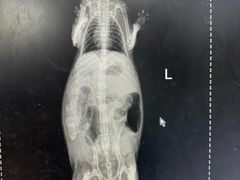

• 瑞派·关忠动物医院·异宠专科·犬猫肿瘤·皮肤专科(望京店)

• -瑞派·关忠动物医院·异宠专科·犬猫肿瘤·皮肤专科(望京店)

匿名用户 | 24-05-05